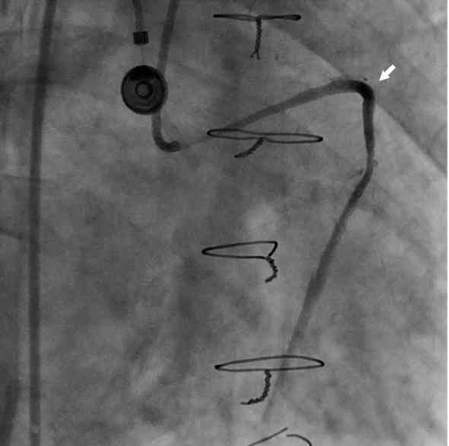

Figure 1. Contrast extravasation with jet stream effect was noted at the dilated site of the saphenous vein graft (SVG; arrowhead) (click thumbnail to view larger image).

A 66-year-old man was admitted to our hospital with acute onset of chest tightness for 2 hours. He had a history of hypertension and end-stage renal disease (ESRD) and had undergone hemodialysis. He also had a 3-vessel coronary artery disease and had undergone coronary artery bypass grafting 1 year prior, receiving a sequential SVG to the right coronary artery (RCA), and obtuse marginal (OM) and left internal mammary artery (LIMA) to the left anterior descending artery (LAD). On physical examination, the patient was found to have a blood pressure of 157/98 mm Hg, heart rate of 84/min, and respiratory rate of 20/min. The cardiovascular examination results were unremarkable. A 12-lead electrocardiogram showed ST elevation in leads II, III, and aVF. Laboratory data showed normocytic anemia and poor renal function, which was related to the ESRD. From the ST elevation, we identified the artery causing the inferior wall acute MI and performed emergent coronary angiography within 90 minutes after the admission. The coronary angiography revealed 61% stenosis at the left main artery, 86% stenosis at LAD, and 77% stenosis at the ostium of the RCA. The bypass graft of LIMA to LAD was patent; however, an 87% stenosis at the proximal SVG to OM2 and RCA was noted. A percutaneous transluminal coronary angioplasty for the SVG lesion was performed immediately, using a 6 Fr JR 4 guiding catheter and EXTRA S’PORT wire (Abbott Vascular Devices). The initial activated clotting time (ACT) was 187 s, and the patient was heparinized with a bolus of 10,000 units before the procedure. First, a Sprinter 2.0 × 20 mm balloon (Medtronic) and then a Firestar 3.0 × 30 mm balloon (Johnson & Johnson) were used to dilate the lesion. Because of unsatisfactory results in comparison with the distal SVG size, a Maverick 4.0 × 30 mm balloon (Boston Scientific) was used next. After a single inflation at 10 atm, contrast extravasation with jet stream effect was noted at the site of the dilation (Figure 1).

There have been only few reports on hemoptysis caused by an SVG aneurysm (SVGA) rupture previously.7-11 According to previous reports, the size of the ruptured SVGA ranged from approximately 2 to 5 cm. Three major different mechanisms are related to the hemoptysis caused by the rupture of an aneurysm. First, the aneurysm densely adherent to the lung had ruptured with bleeding into the pleura and lung parenchyma. Large hematoma eroding into the lung tissue could cause hemoptysis.9,10 Second, a fistula developed between a vein graft aneurysm and the bronchial trees.7,8 Hemoptysis is caused by bleeding from the aneurysm into a segmental bronchus. Third, the SVGA connected to lung parenchyma with no evidence of fistula.11 To our knowledge, this is the first report of such a case of hemoptysis after an SVG rupture due to coronary intervention. The cardiac CT image showed no evidence of fistula between the vein graft and a bronchus or the existence of direct connection between the proximal SVG and the lung parenchyma or bronchial trees. Only a thin layer of tissue between the SVG and lung parenchyma was noted from the CT reconstruction image; therefore, the SVG may be densely adherent to the lung. The coronary angiography revealed contrast extravasation with jet stream effect at the site of balloon dilation. Comparing the reconstructed CT image with the coronary angiographic image from a similar angle, we speculate that blood jet stream from the SVG graft perforation could have directly leaked into the lung tissue, causing the hemoptysis.